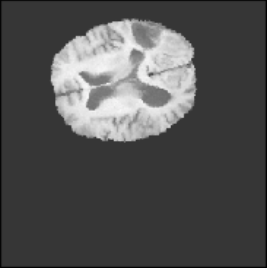

(a) Fixed (T2)

Figure 3: Intra and Inter modality MR registration. Time taken: 0.21 sec

To illustrate the performance of the proposed technique for clinical applications, MR images were chosen. The performance of the technique was tested by registering multi-modal MR image pairs. In a clinical setup, it is common practice to register images or volumes acquired from different imaging modalities or MR sequences. Figure 3 illustrates the degree of overlap between moving images (a) T2 and (f) T1 weighted sequence on fixed images (b) T2 and (g) T2 weighted sequence respectively. It was observed using the registration proposed in this manuscript, the dice score improved from 0.44 (prior to registration) to 0.91 (post registration) for multimodal sequences. On the BraTs data, figure 4 (a-d) illustrates the performance of our method based on other metrics such as Dice, SSMI, MI, and MSE respectively. As the key points were generated by utilizing only the feature maps of the initial two layer of the network, the spatial dimension of the data has little impact on the performance. Unlike other CNN based technique which considers the entire image for estimating the transformation parameters, our method requires CoMs which reduces the dimensionality from (m ×\times n ×\times n) to (m ×\times 2), where m denotes the number of feature maps and n is the pixel dimension of the feature map. This aids in lowering execution time drastically. The proposed pipeline also consists of an uncertainty estimator. uncertainty maps illustrated in all the above examples show the region of higher variance in registration, which in turn suggests surgeons/ observers to make better decisions. Pixel region with red color indicates the larger variance region while blue indicated low variance region. For example in figure 3 (e) shows that the central region of the brain has higher pixel-wise variance as compared to the outer part of the brain. The performance of the algorithm on volumes on the same modality is illustrated in figure 3 (a-e)